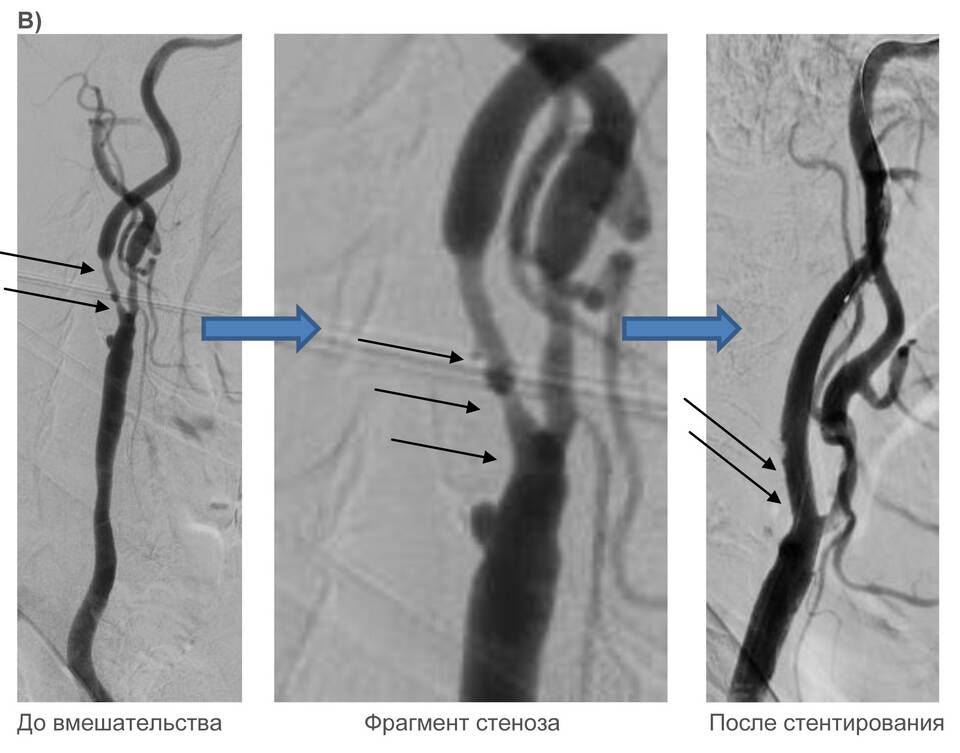

Методы диагностики

1. Ультразвуковая допплерография

2. Компьютерная томографическая ангиография

3. Магнитно-резонансная ангиография

4. Коронарография (для сердечных сосудов)